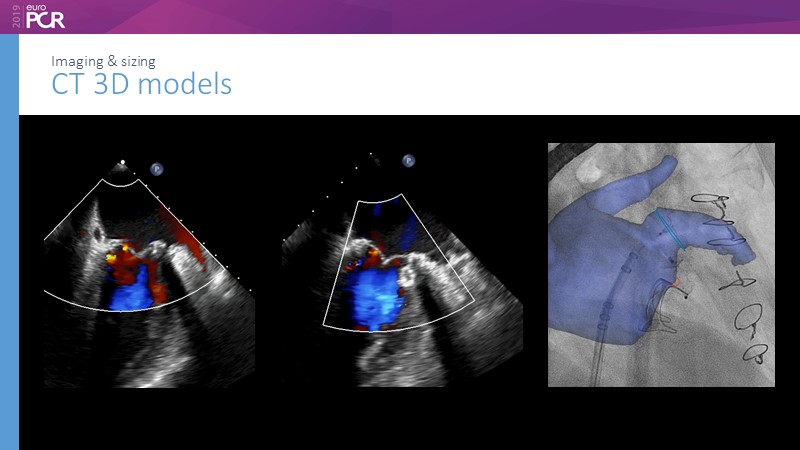

Pre-procedure planning

Previous Next